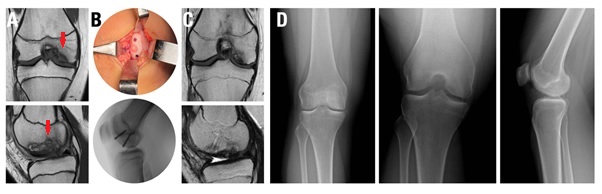

En promedio, se trasplantaron entre 1 y 3 injertos osteocondrales cilíndricos por rodilla, con un diámetro promedio de 8 mm (rango, 6-10 mm). Diecisiete rodillas se trataron para DC (Fig. 1) y 16 mediante FH (Fig. 2) de lesiones osteocondrales inestables. Las lesiones tratadas con la técnica DC tuvieron un tamaño promedio de 132 mm2, significativamente menor que las lesiones de FH, con un tamaño promedio de 404.1 mm2 (p <0.0001). El seguimiento promedio de la cohorte fue de 20.5 meses (rango, 6-80 meses). No se registraron complicaciones perioperatorias.

Figura 1. Trasplante osteocondral autólogo en una paciente de 10 años con defecto osteocondral de cóndilo femoral externo. A) Imagen preoperatoria de RNM DPFS (coronal) y T1 (sagital) donde se observa el defecto (flecha amarilla). B) RNM DPFS (coronal) y T1 (sagital) a los 6 meses, se observa incorporación completa del injerto.